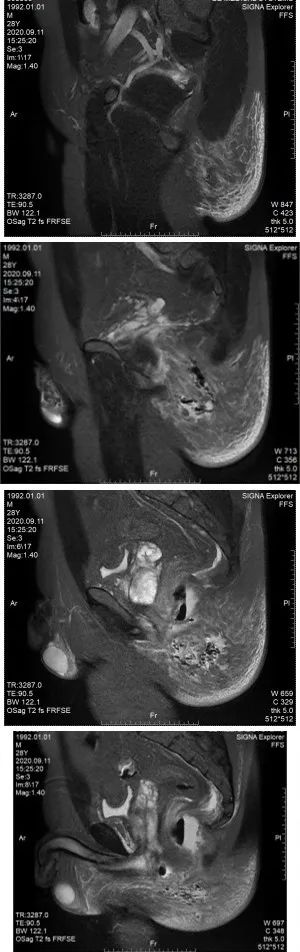

肛肠科主任医师再次查看病人,此时肛周MRI结果回示:直肠周围及左臀部、会阴部异常信号,考虑肛周脓肿并周围软组织水肿,建议增强扫描检查。图附下。

可见气液平面及组织间隙气体

白细胞及c反应蛋白均较前增高,且白细胞超过20×10^9/L,出现低蛋白血症,血红蛋白降低(贫血征兆),出现低钠、低钙电解质紊乱。感染较前次增加,提示重度感染,查看患者臀部红肿范围,1点位肿块红肿更加明显,范围较前增大,左侧臀部红肿范围亦有向后背部扩展迹象。结合肛周MRI,左侧臀部及会阴部皮下脂肪间隙模糊,见片状长T1长T2信号影,边缘不清,局部见斑片状气体密度影。主任医师查看病人后考虑:患者有坏死性筋膜炎可能,应立即行手术治疗,避免感染性休克及炎症的快速扩散导致生命危险。